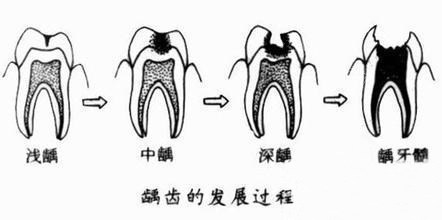

儿童舒适化涂氟/窝沟封闭:采用美国3M防龋材料,搭配“星星奖励贴”“动画投影”等互动方式。适合2岁以上牙齿萌出的宝宝,能降低70%龋齿发生率。有宝妈分享:“带2岁半宝宝来做涂氟,医生用小熊玩偶演示,宝宝全程配合,结束还问‘什么时候再来玩’。”

早期咬合干预(MRC肌功能训练):使用澳大利亚进口MRC矫治器,通过调整口周肌肉功能改善龅牙、地包天等问题。适合3-12岁处于生长发育期的儿童,矫正周期比传统牙套缩短1/3。有位4岁宝宝因口呼吸导致牙齿前突,佩戴MRC半年后,家长反馈“睡觉闭唇了,牙齿排列也变整齐”。